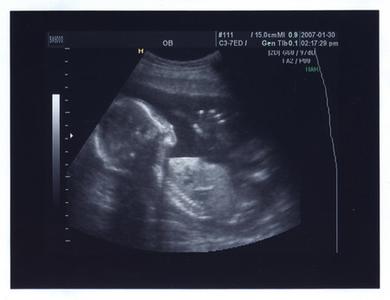

B型超声波检查:最早在妊娠第5周,亦就是月经过期一周,在B型超声波屏上就可显示出子宫内有圆形的光环,又称妊娠环,环内的暗区为羊水,其中还可见有节律的胎心搏动。用B超诊断早孕是最正确可靠的方法。

凯里恒生医院引进的日本东芝660A彩超(xario赛锐)为TOSHIBA公司最新研发的超高档临床实用性彩色多普勒超声诊断仪。

作为最新一代的高档超声产品,Xario采用最新的智能化组件设计理念,全新的开放式结构,创新的成像技术和应用,全部体现了东芝超声最新的先进科研成果,提供高质量的所有模式的超声影像:2D模式、M模式、CDI(彩色多普勒成像)模式(血流谱)、多普勒模式及实时三维成像(四维)技术,仪器配置多功能探头:如腹部妇科探头、心脏探头、阴道腔内探头及高频探头,可以适应不同器官检查需要,为临床诊断和科研提供了一个强有力的平台。使用该产品能够准确检测出女性是否怀孕。您明白了吗?点击这里,咨询在线专家